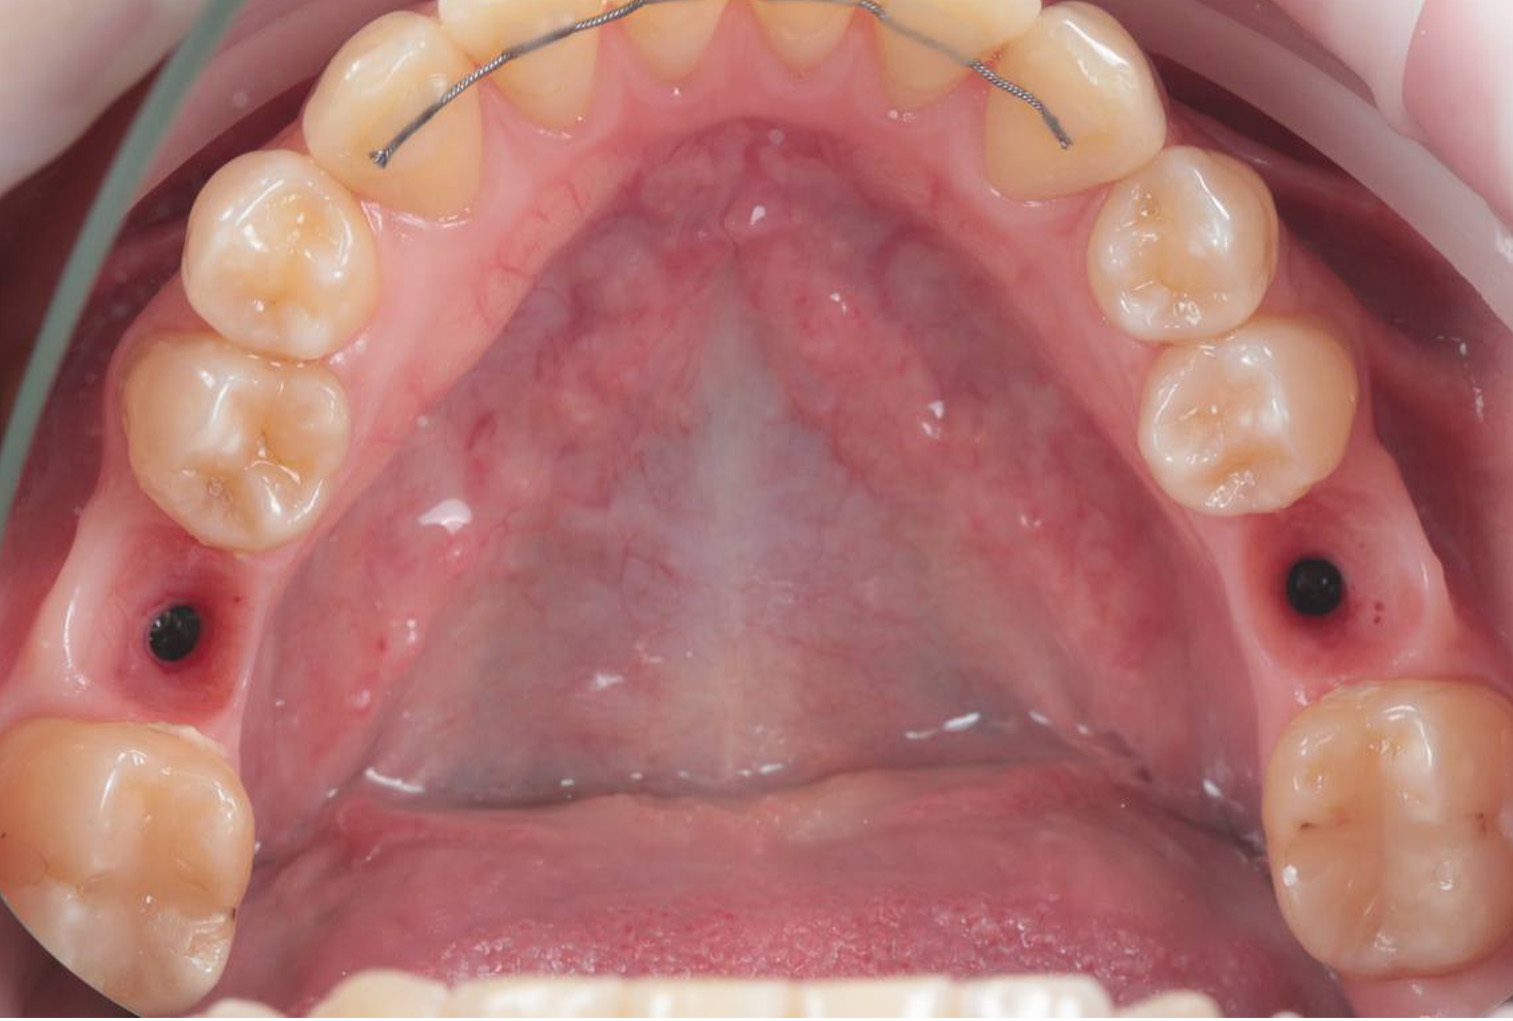

Пациент обратился с жалобами на отсутствие 36 и 46 зуба, что значительно затрудняло прием пищи. Также наблюдалась выраженная атрофия мягких тканей и тонкая кость в данной области.

Была успешно проведена имплантация зубов, без необходимости в костной пластике После установки имплантатов было выполнено протезирование коронками из диоксида циркония, которые были изготовлены в собственной цифровой зуботехнической лаборатории “ Протетика”.